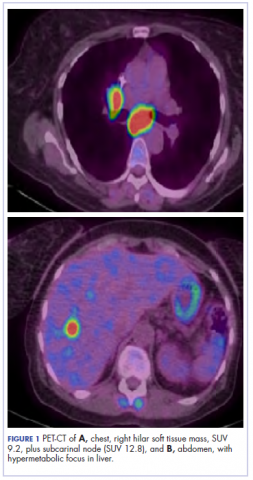

The patient underwent a CT-guided core biopsy of the spiculated nodule, which was found to be consistent with adenocarcinoma of the lung. It was negative for EGFR mutation or ALK rearrangement. She received stereotactic radiosurgery to the left posterior parietal lesion, and after completion of radiation, was started on systemic chemotherapy with cisplatin plus pemetrexed for adenocarcinoma of the lung. She received 4 cycles of chemotherapy. Repeat imaging with a PET-CT showed interval increase of the mediastinal hypermetabolic lymphadenopathy with new hypermetabolic pretracheal lymph nodes and interval development of multiple liver metastases in the right and left lobes of the liver (Figure 1). She was started on second-line therapy with nivolumab at a dose of 240 mg every 2 weeks. The treatment was complicated initially by new onset grade 2 papular pruritic rash after cycle 2 of therapy. The rash involved the upper and lower extremities, sparing the palms, soles, trunk, abdomen, and the back. It resolved with treatment delay and topical steroids.

Figure 1. PET showing soft tissue mass